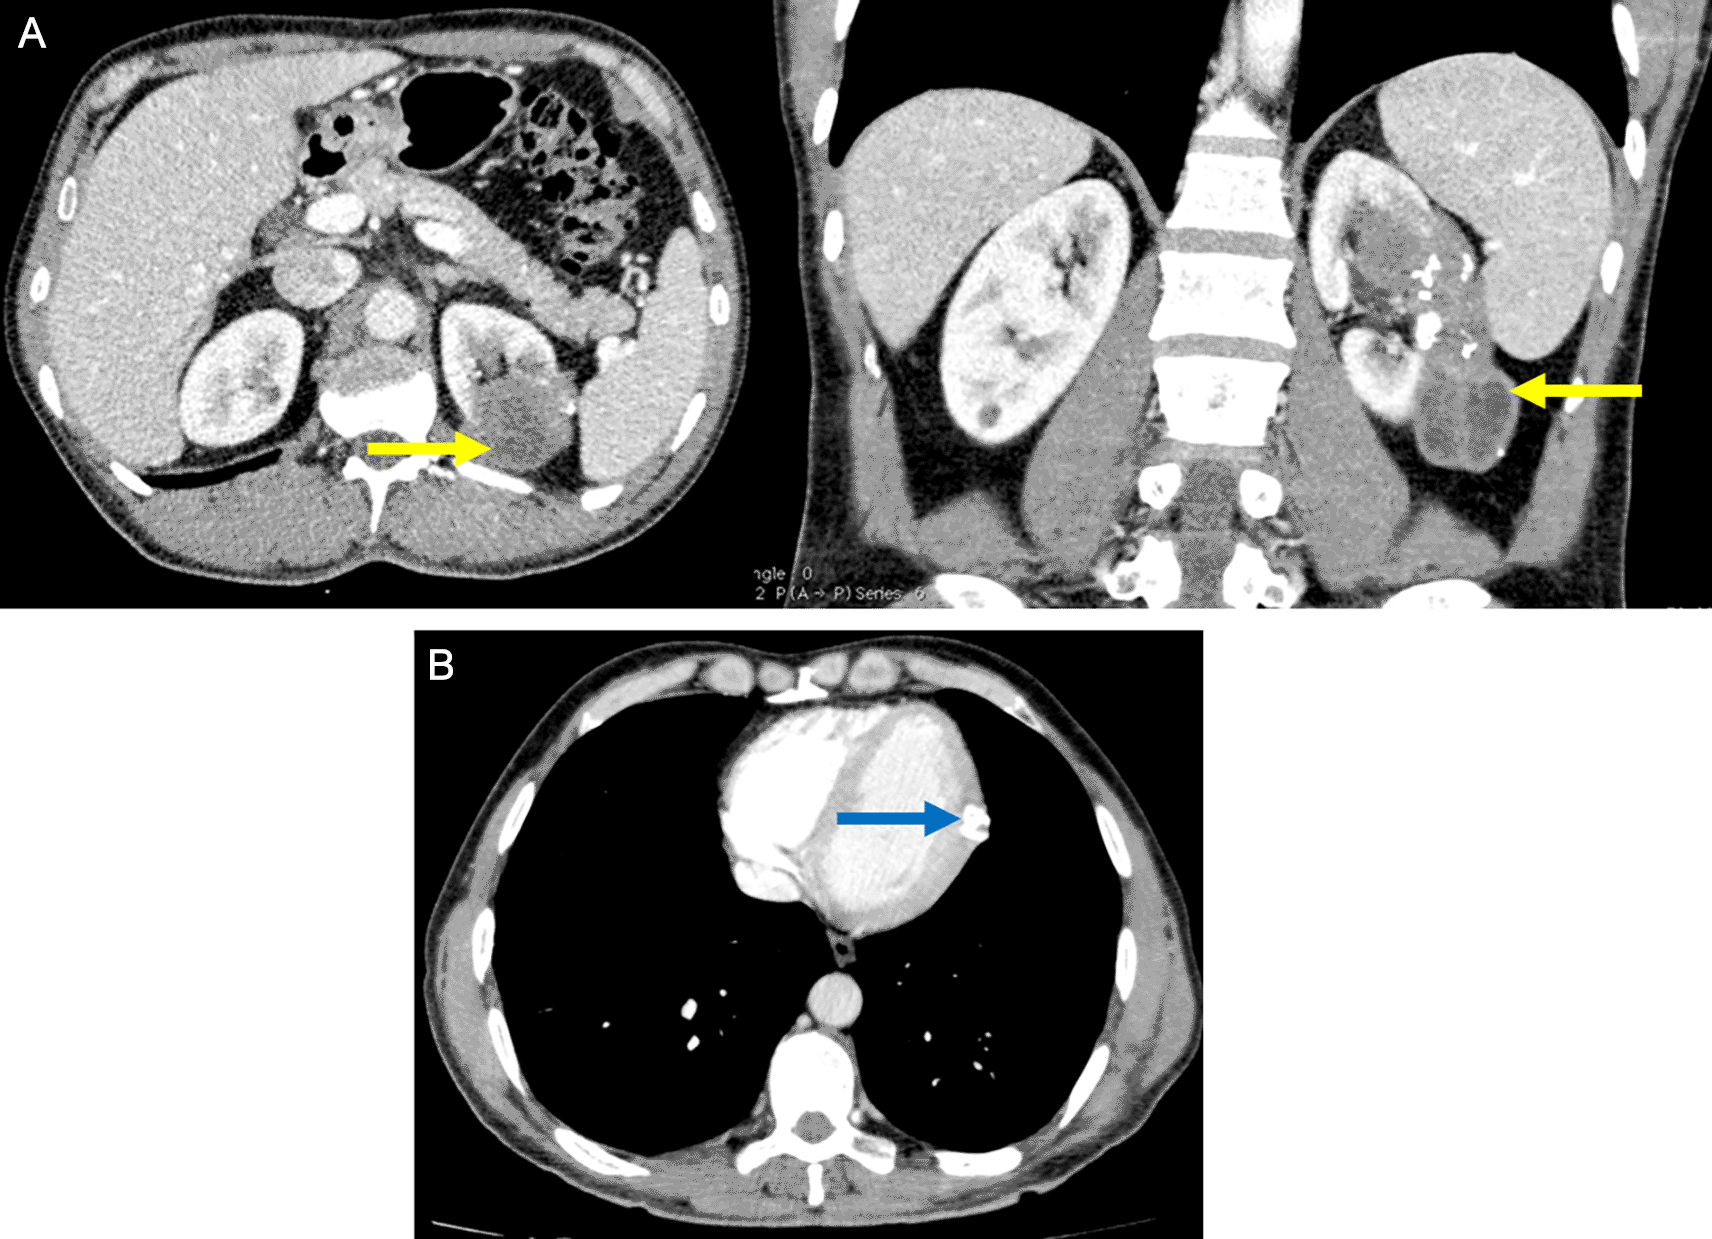

The patient was followed up at the department of abdominal surgery, a multiple organ hydatidosis including 13 hydatid cysts were discovered: the lungs, the liver ( Figure 1), the left heart ventricle, the left kidney (Figure 2), the abdomen cavity, the muscles (psoas, adductors), and the subcutaneous gluteal area. In fact, the patient has been experiencing at the beginning a bronchial syndrome symptom, including coughing, and hemoptysis. The laboratory tests were performed and were within the normal range except for high hydatid serology. A Chest CT scan showed three lungs’ cysts. With the exception of the psoas cyst, which is associated with a lower limb paresthesia, the remaining cyst locations identified above were discovered during the preoperative search for additional cysts sites.

Renal involvement is also rare (2–3%) and it is usually associated with disseminated disease, they are most commonly asymptomatic, as reported in the present case. The diagnosis was made by an abdominal CT scan which has a sensitivity of 98% in diagnosing hydatid disease.8

Psoas cysts are also uncommon.9 The patient presented with two psoas cysts, a finding that has never been reported in the literature.